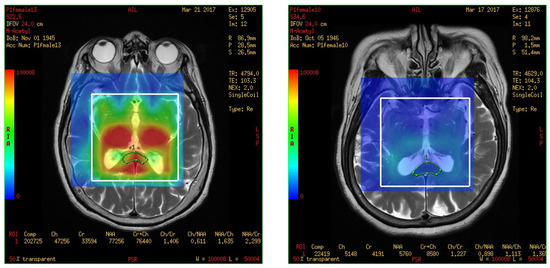

In this study, a medical 1.5 T MRI machine (GE Signa HDxt Medical Systems, Waukesha, WI, USA) and a standard head coil (Head Coil) in Camillians Saint Mary’s Hospital Luodong were used to receive signals from brain images of MRI T1 and T2 sequences, and 1H-MRS with 3D-CSI (echo time (TE) 144 ms, repetition time (TR) 1000 ms) for all participants. The range of chemical shift was set from 0 to 4 ppm, as this could include the signal of most metabolites in the brain, and the volume of each voxel was set at approximately 1–1.5 square centimeters. The measurements were performed as follows: First, brain images of T1 and T2 sequence with 3-Plane localization (sagittal, axial, and coronal planes) were obtained to locate the hippocampus and corpus callosum in the brain. Second, the three-dimensional space of the hippocampus and corpus callosum was manually marked and chosen on the image by a technician. Subsequently, the three-dimensional space of the hippocampus was divided into the total (bilateral), right, and left hippocampi. Third, the MRS with 3D-CSI was performed in the chosen location of the hippocampus (Figure 1) and corpus callosum (Figure 2). The signal intensities of choline (Cho), N-acetyl aspartate (NAA), creatine (Cr), and myo-inositol (MI) in the total (bilateral), right, and left hippocampi and the corpus callosum were measured and recorded in arbitrary units and used for statistical analysis.

Figure 2.

Magnetic resonance spectroscopy with three-dimensional chemical shift images in the chosen location of the bilateral corpus callosum (green markup). The signal intensities of metabolites were measured and recorded.